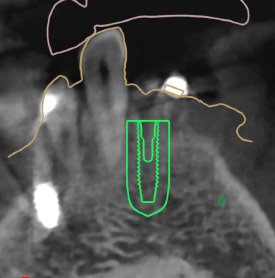

덴티스 - 심플가이드

오스템 - 원가이드

디오 - 디오나비